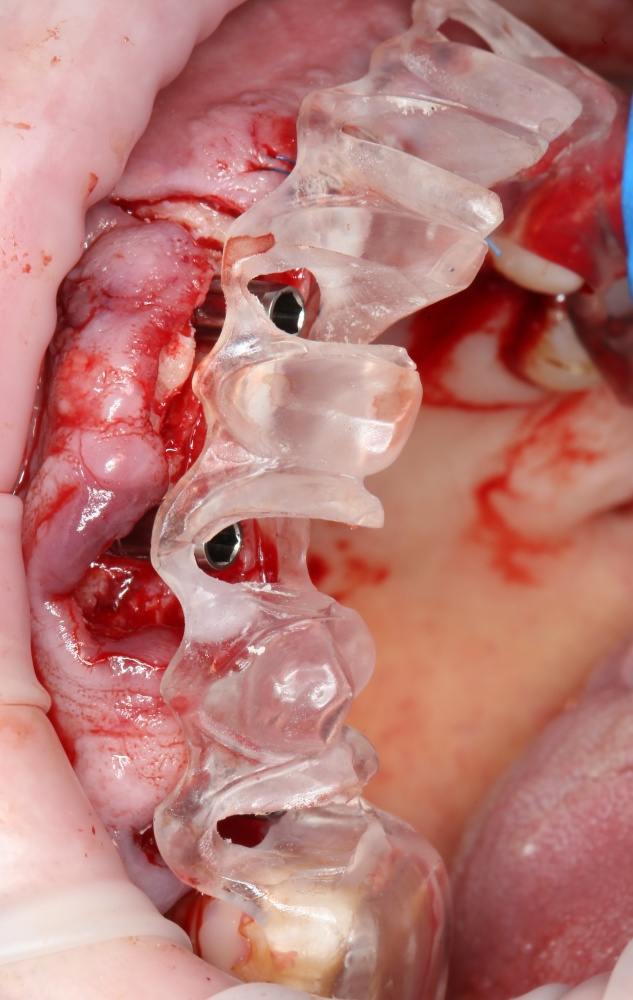

Рекомендации по установке имплантов. Для всех. Часть V.